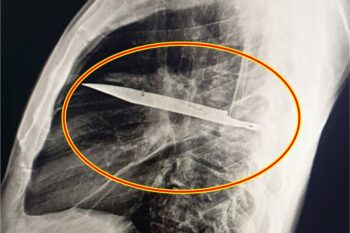

Passenger Armed With Knife at Iloilo Airport Shot A 54-year-old passenger was shot in the chest at Iloilo International Airport in Cabatuan, Iloilo, on Wednesday afternoon after being found carrying a knife. The incident occurred around 4:44 p.m. in the pre-departure security screening area. According to the Office for Transportation Security (OTS), a security officer … Read more